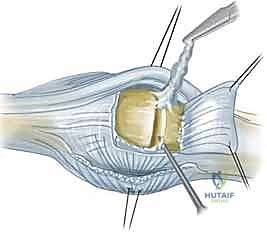

استئصال الغشاء الزليلي وتوسيط الوتر الباسط لمفصل MCP هو إجراء جراحي يعالج انحراف الأصابع وتشوهها الناتج عن التهاب المفاصل، خاصة الروماتويدي. يهدف إلى تخفيف الألم، استعادة ميكانيكا المفصل، وتحسين وظيفة اليد من خلال إزالة الأنسجة الملتهبة وإعادة محاذاة الأوتار.

الخلاصة الطبية السريعة: يُعد إجراء "استئصال الغشاء الزليلي وتوسيط الوتر الباسط لمفصل MCP" بمثابة طوق النجاة الجراحي الفعال لعلاج انحراف الأصابع وتشوهاتها المعقدة الناتجة عن التهاب المفاصل، وعلى رأسها التهاب المفاصل الروماتويدي. يهدف هذا التدخل الجراحي الدقيق إلى القضاء على الألم المزمن، واستعادة الميكانيكا الحيوية للمفصل، وتحسين الوظيفة الحركية لليد بشكل جذري. يتم ذلك من خلال الإزالة الدقيقة للأنسجة الزليلية الملتهبة (التي تدمر الغضاريف) وإعادة محاذاة الأوتار الباسطة المنزلقة إلى مسارها التشريحي الصحيح. تحت إشراف جراح خبير، تعود لليد قدرتها على أداء المهام اليومية بكفاءة ومظهر طبيعي.

في مركزنا، وتحت إشراف الأستاذ الدكتور محمد هطيف، ندرك تماماً حجم المعاناة الجسدية والنفسية، والتحديات الوظيفية الهائلة التي يواجهها مرضانا بسبب هذه الحالة المتقدمة. لذلك، نقدم حلاً جراحيًا متطوراً ومتخصصاً يُعرف باسم استئصال الغشاء الزليلي وتوسيط الوتر الباسط لمفصل MCP. هذا الإجراء الميكروسكوبي الدقيق مصمم بعناية فائقة لاستعادة ميكانيكا المفصل الطبيعية، إيقاف التدمير الغضروفي، تخفيف الألم بشكل نهائي، وتحسين وظيفة اليد ومظهرها بشكل ملحوظ للمرضى الذين يتم تقييمهم واختيارهم بعناية.

- التهاب الغشاء الزليلي (Synovitis): يبدأ المرض بالتهاب الغشاء الزليلي، وهو الغشاء الرقيق الذي يبطن المفصل ويفرز السائل الزليلي للتشحيم. في مريض الروماتويد، يتكاثر هذا الغشاء بشكل مرضي ويصبح سميكاً جداً.

- تكوين السبلة (Pannus Formation): يتحول الغشاء الزليلي الملتهب إلى نسيج عدواني يُعرف باسم "السبلة" (Pannus). هذا النسيج يفرز إنزيمات مدمرة (مثل الميتالوبروتياز) تأكل الغضروف المفصلي الناعم وتسبب تآكلات (Erosions) في العظام تحت الغضروف.

- الانزلاق الزندي للوتر الباسط (Ulnar Subluxation of EDC): بمجرد ضعف الرباط السهمي الكعبري، ينزلق وتر الباسطة (EDC) من أعلى قمة المفصل نحو الوادي الزندي بين الأمشاط. عندما يحدث هذا، يفقد الوتر قدرته على بسط الإصبع بفعالية، وبدلاً من ذلك، تصبح قوة سحبه مساهمة في زيادة الانحراف الزندي للأصابع.